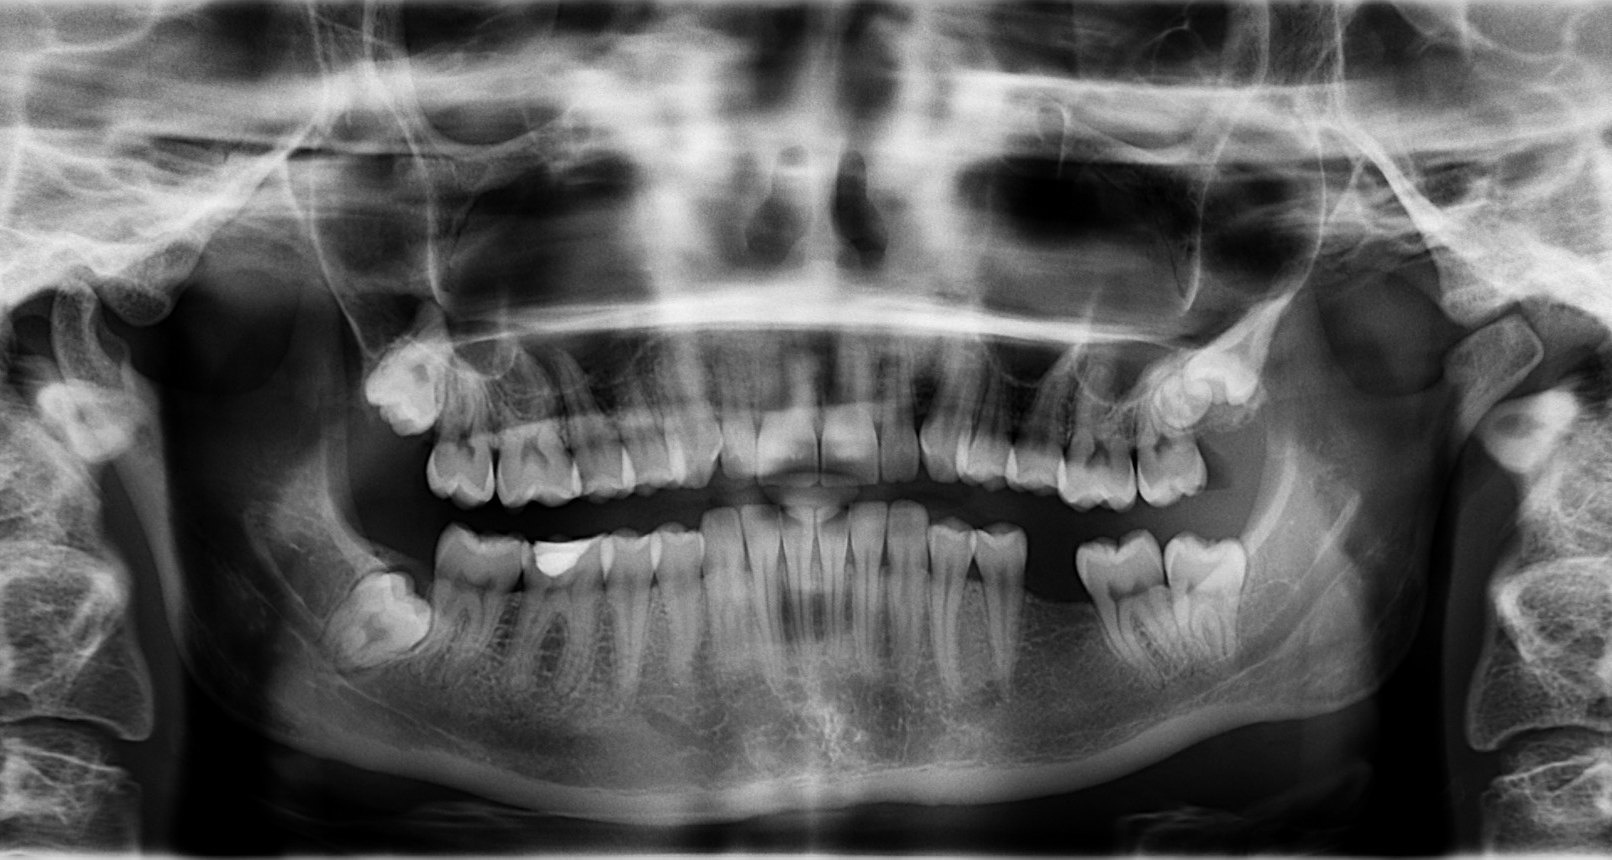

Зубы состоят из кальция, фосфора и других минералов. Кости тоже содержат кальций с фосфором, но в основном состоят из белкового коллагена. Коллаген - это живая, растущая ткань, которая дает костям относительно гибкий каркас. Кальций заполняет пространство вокруг каркаса и делает кость достаточно прочной, чтобы выдерживать вес тела и другие нагрузки.